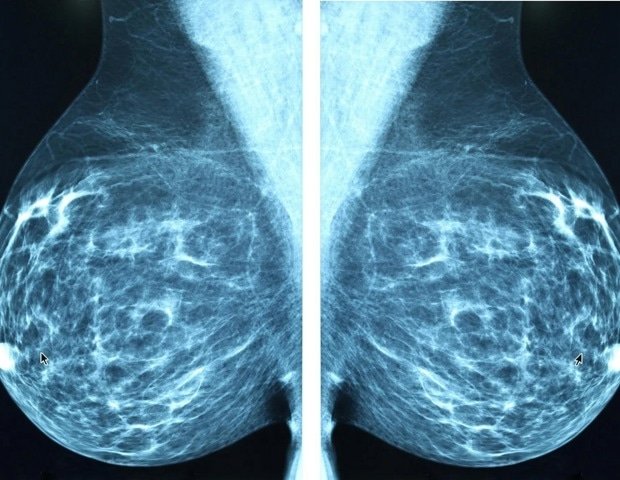

Brain metastasis is a common complication of advanced breast cancer, with a particularly high risk in inflammatory breast cancer. However, there are no effective treatments because the underlying mechanisms remain poorly understood.